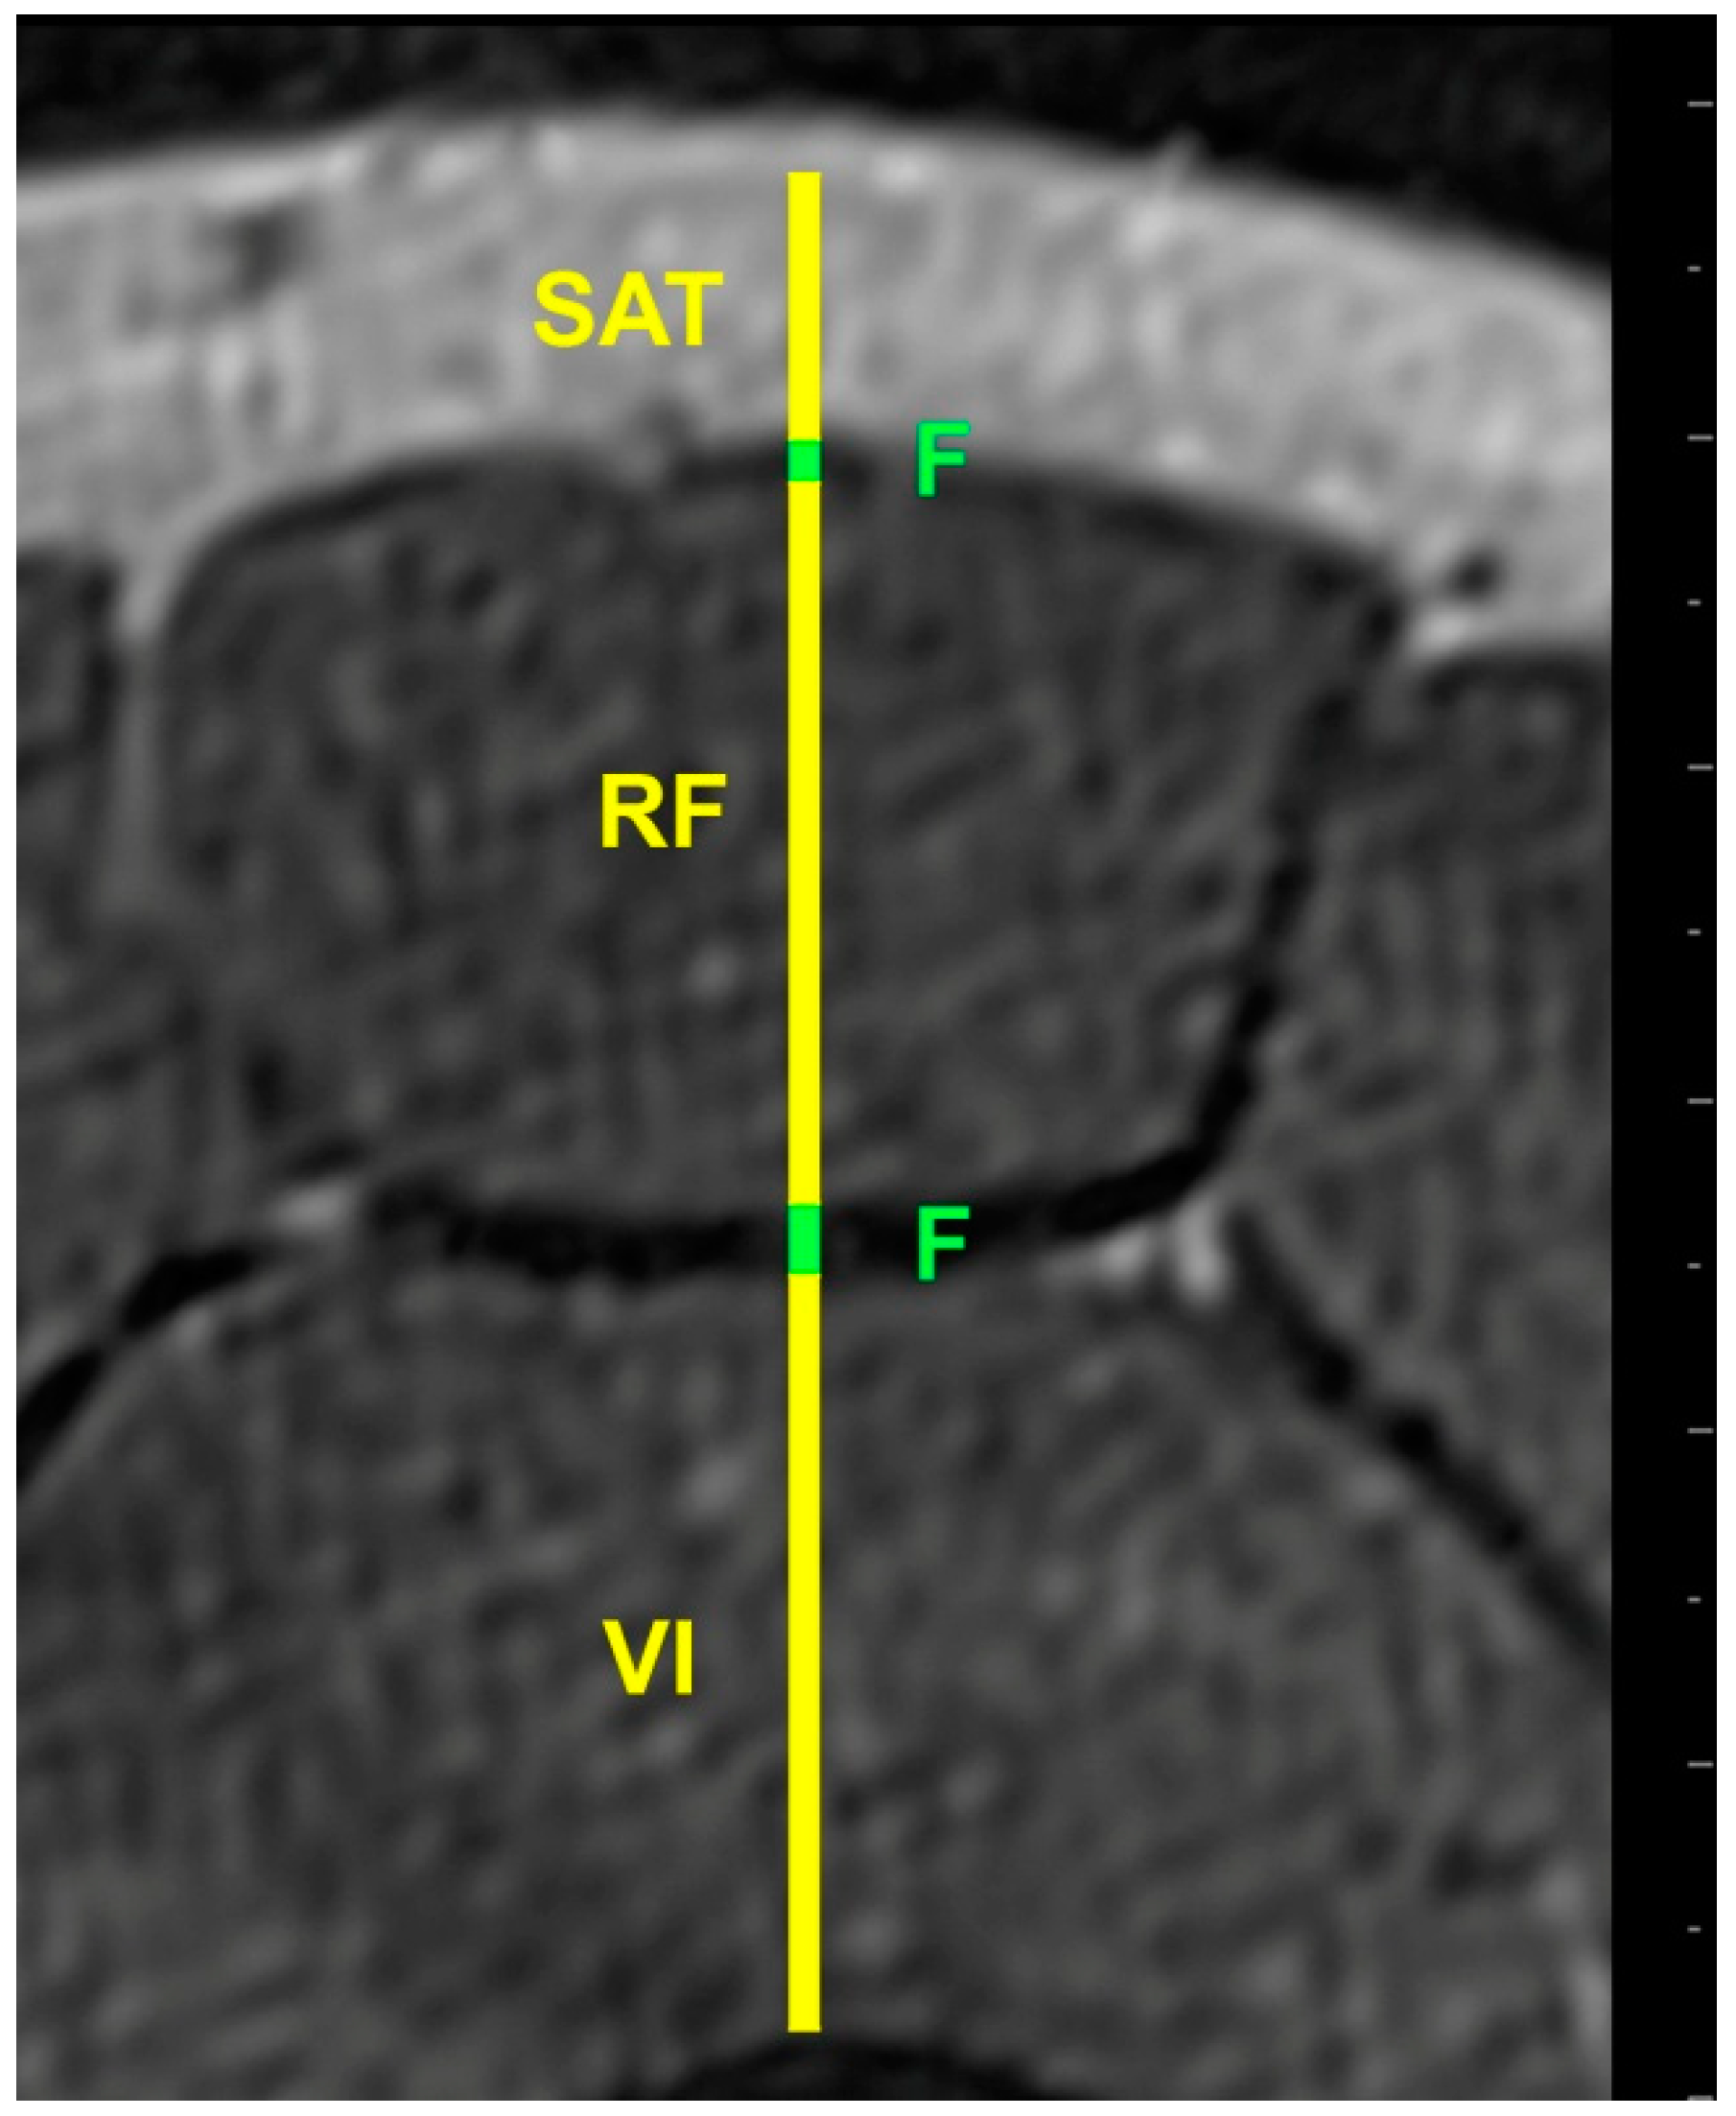

2.4. MRI Acquisition

2.5. Image Processing

- Hides, J.; Wilson, S.; Stanton, W.; McMahon, S.; Keto, H.; McMahon, K.; Bryant, M.; Richardson, C. An MRI Investigation into the Function of the Transversus Abdominis Muscle During “Drawing-In” of the Abdominal Wall. Spine 2006, 31, E175–E178. [Google Scholar] [CrossRef] [PubMed]

- Mendis, M.D.; Wilson, S.J.; Stanton, W.; Hides, J.A. Validity of Real-Time Ultrasound Imaging to Measure Anterior Hip Muscle Size: A Comparison with Magnetic Resonance Imaging. J. Orthop. Sports Phys. Ther. 2010, 40, 577–581. [Google Scholar] [CrossRef] [PubMed]

- Worsley, P.R.; Kitsell, F.; Samuel, D.; Stokes, M. Validity of measuring distal vastus medialis muscle using rehabilitative ultrasound imaging versus magnetic resonance imaging. Man. Ther. 2014, 19, 259–263. [Google Scholar] [CrossRef] [PubMed]